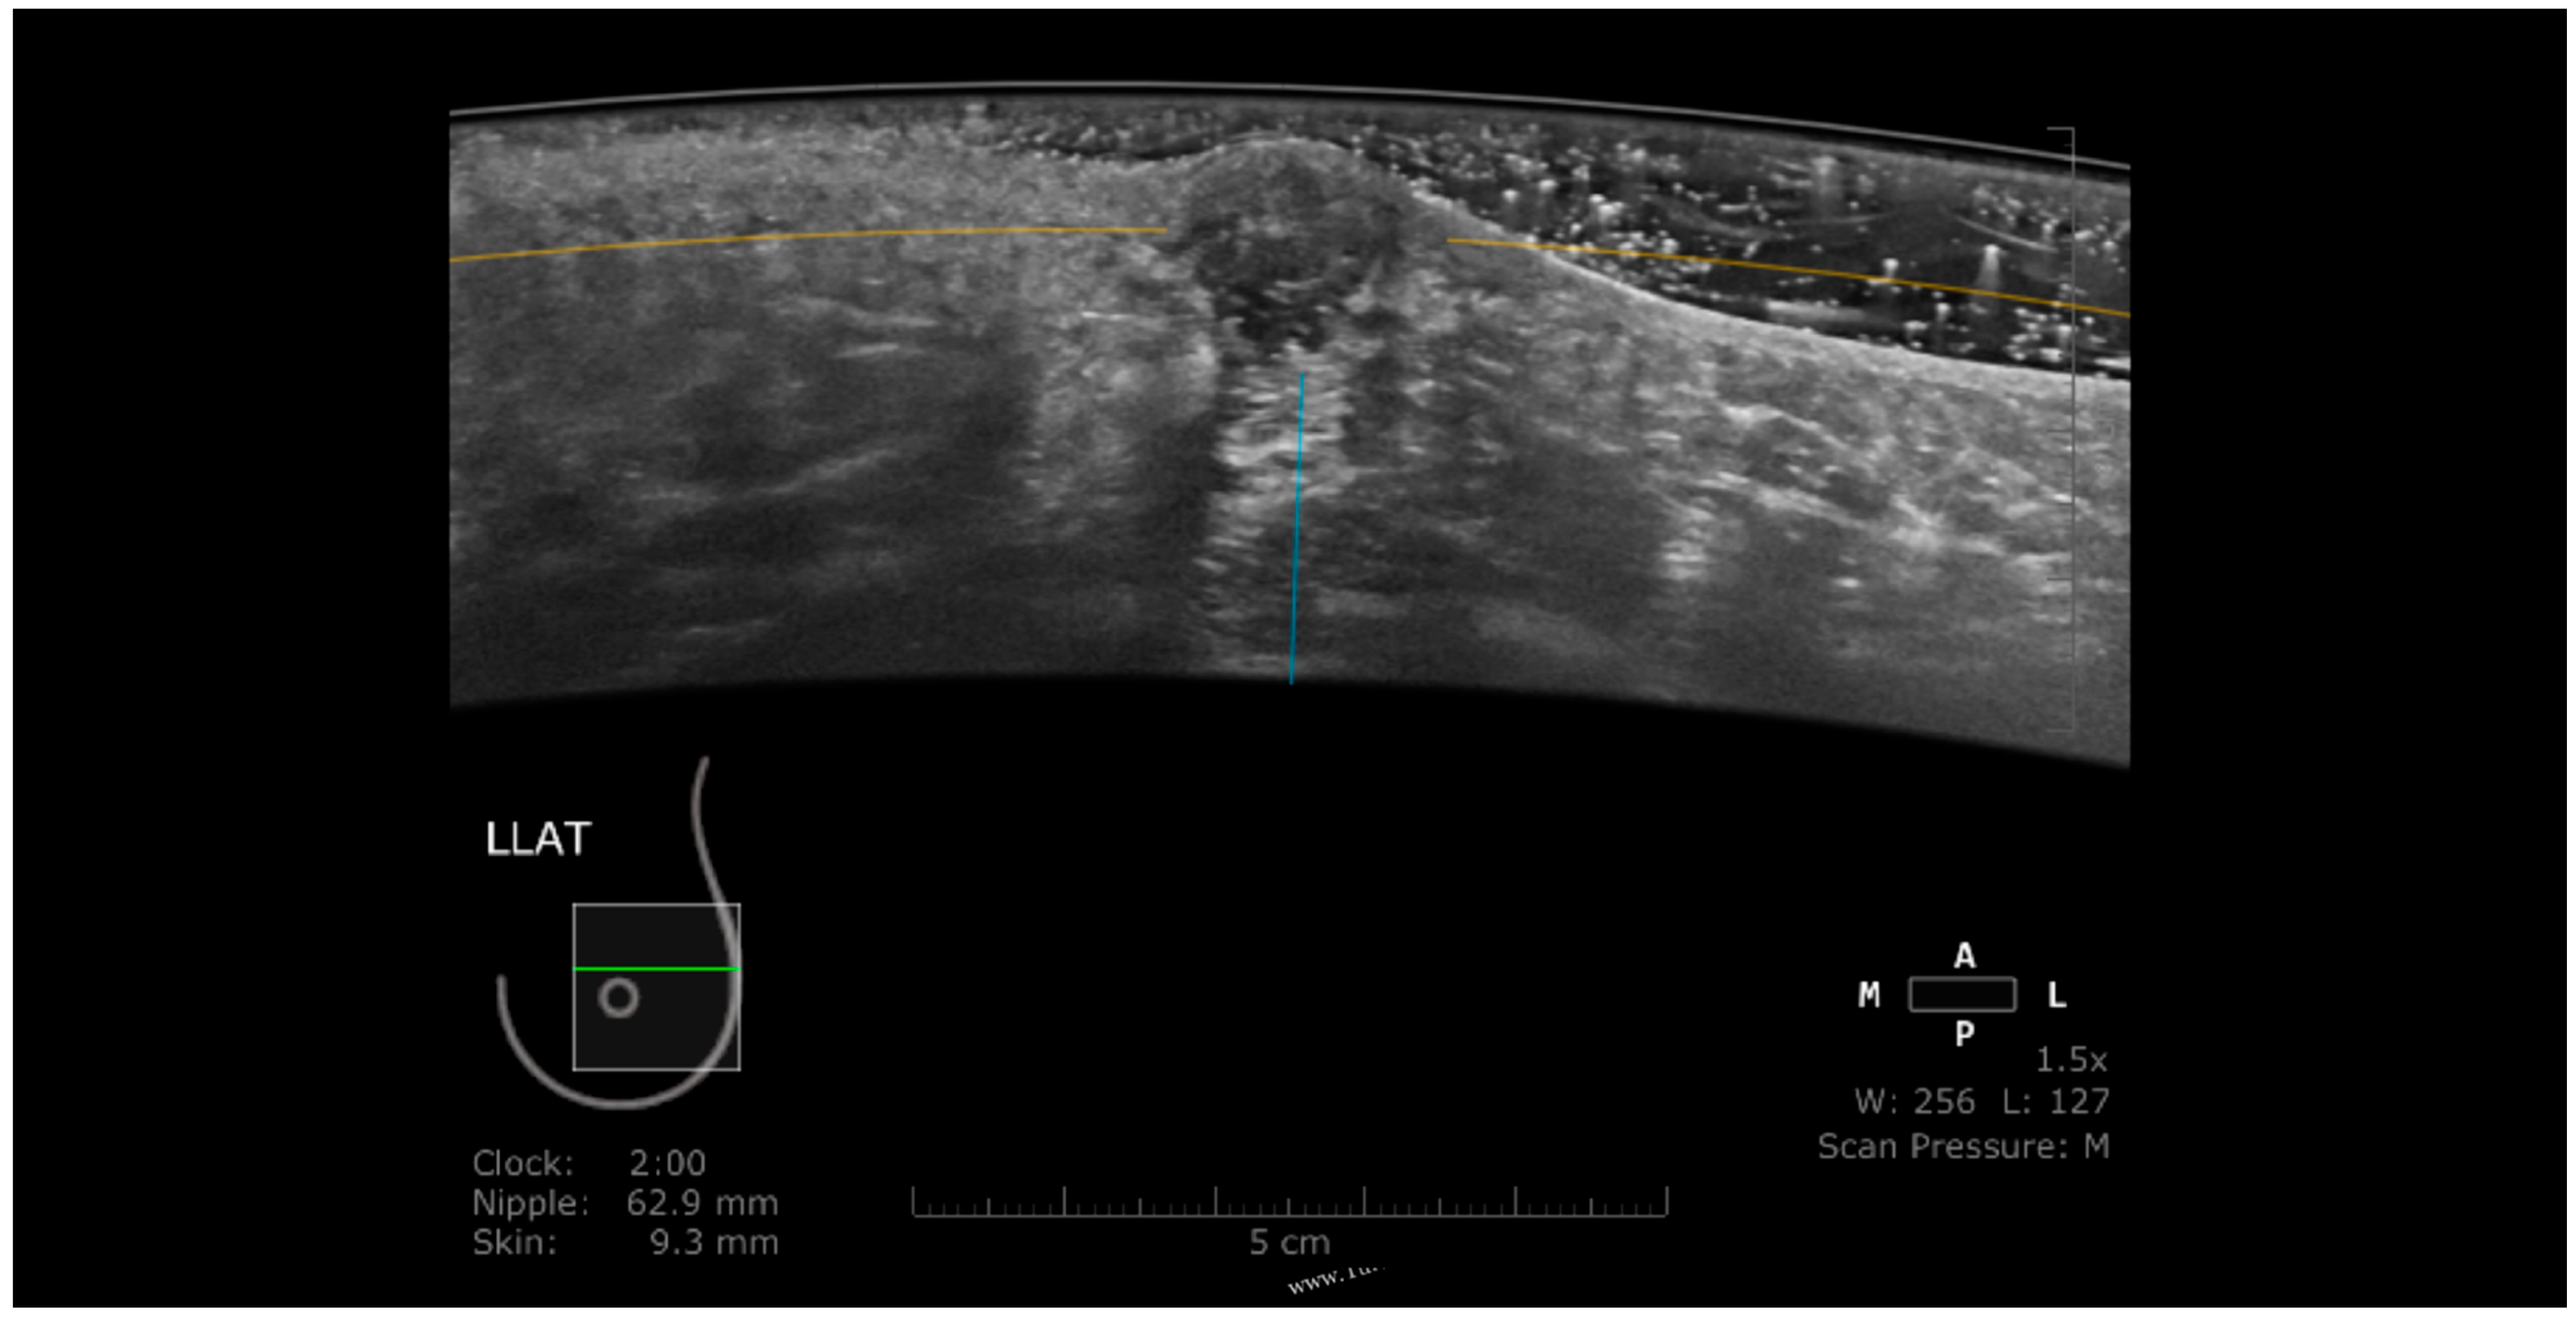

Nipple Artifact

- Isobe, S.; Tozaki, M.; Yamaguchi, M.; Ogawa, Y.; Homma, K.; Satomi, R.; Saito, M.; Joo, C.; Fukuma, E. Detectability of breast lesions under the nipple using an automated breast volume scanner: Comparison with handheld ultrasonography. JPN J. Radiol. 2011, 29, 361–365. [Google Scholar] [CrossRef] [PubMed]